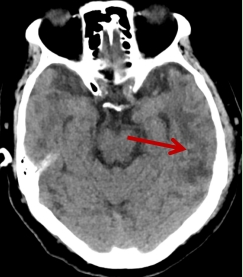

术后在ICU密切配合监护治疗下,患者症状完全缓解,很快恢复到患病前的状态,能进行正常活动,无任何并发症发生。术后病理报告为肺源性转移瘤,与家属认真沟通后尊重家属意愿不再后续治疗。患者现已出院,在四川泰康医院的治疗下,患者延长生命长度的同时,也提高了生存质量。

图4 术后复查头部CT(肿瘤切除彻底,脑水肿明显减退)